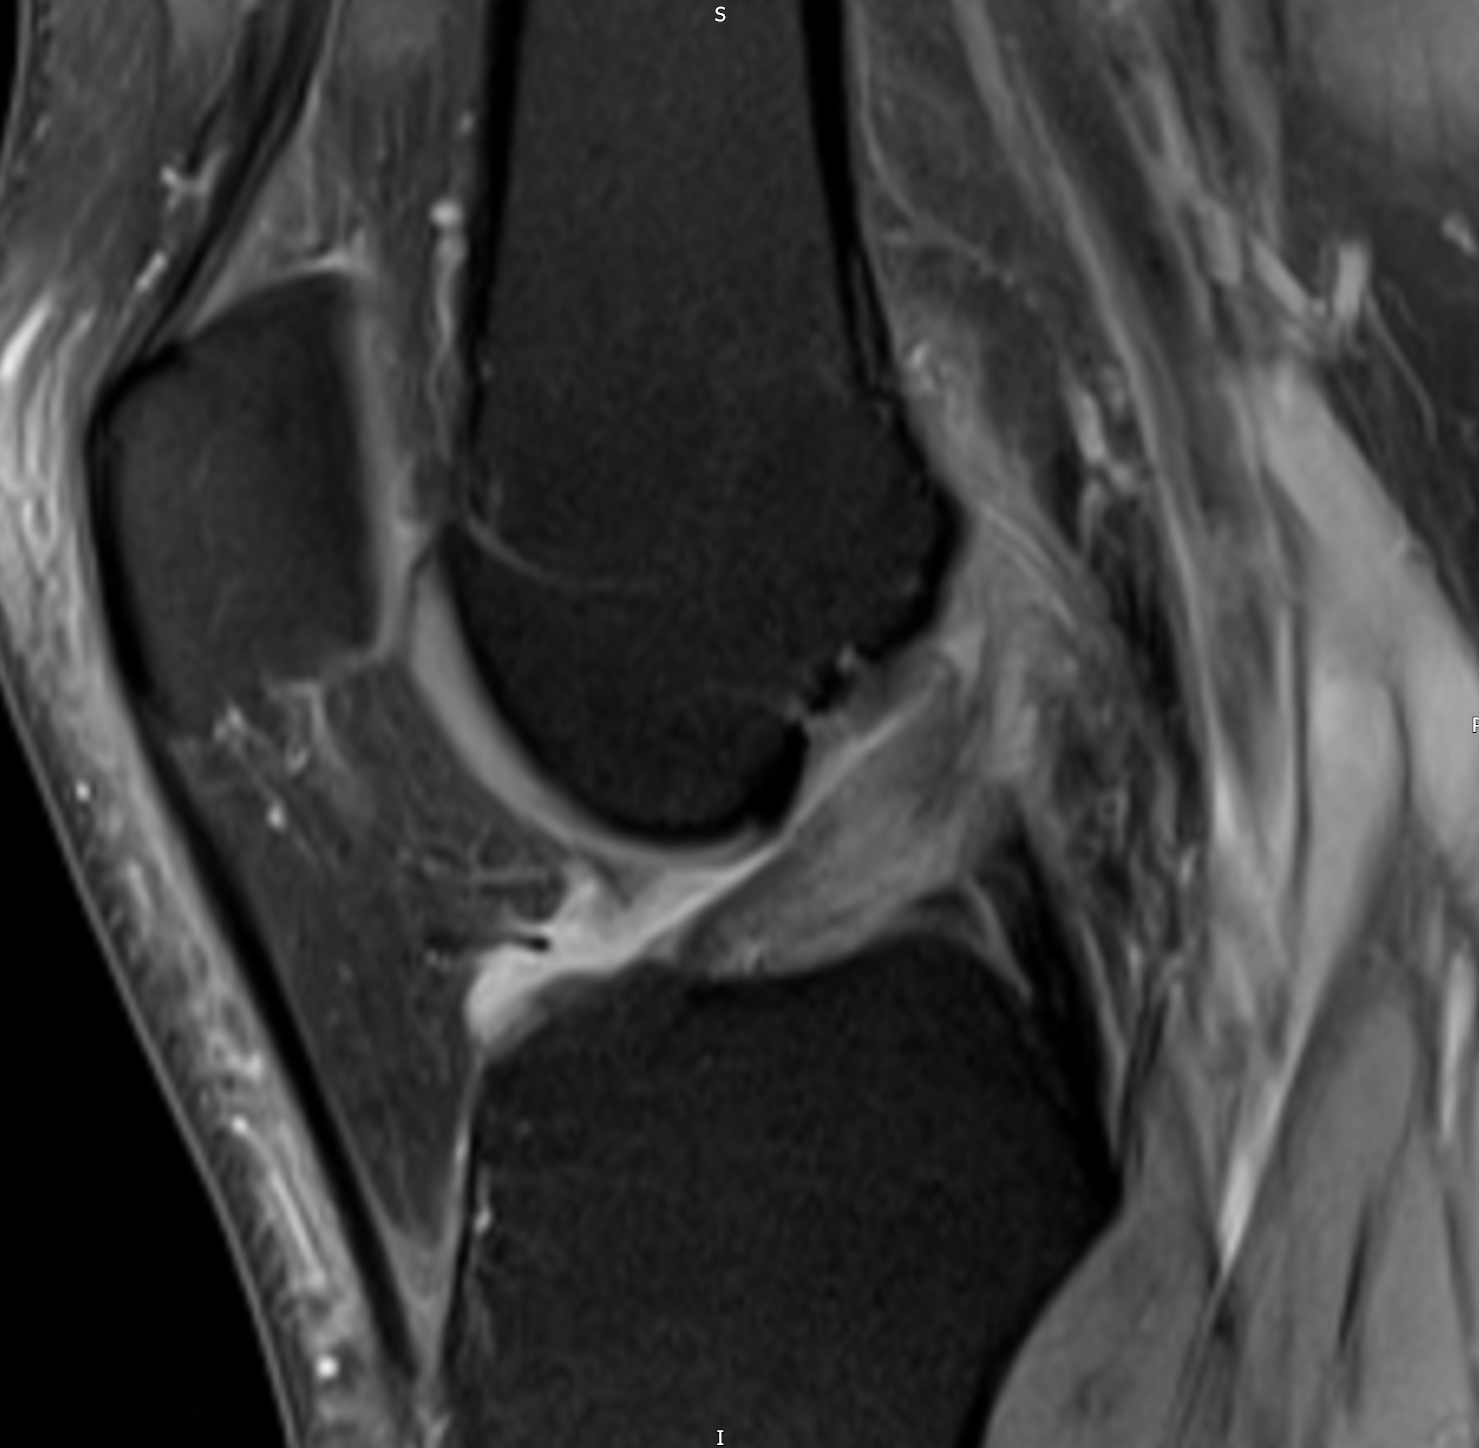

| PD FS Cor: There is a narrow fluid streak between the ACL fibres and the lateral condyle. |